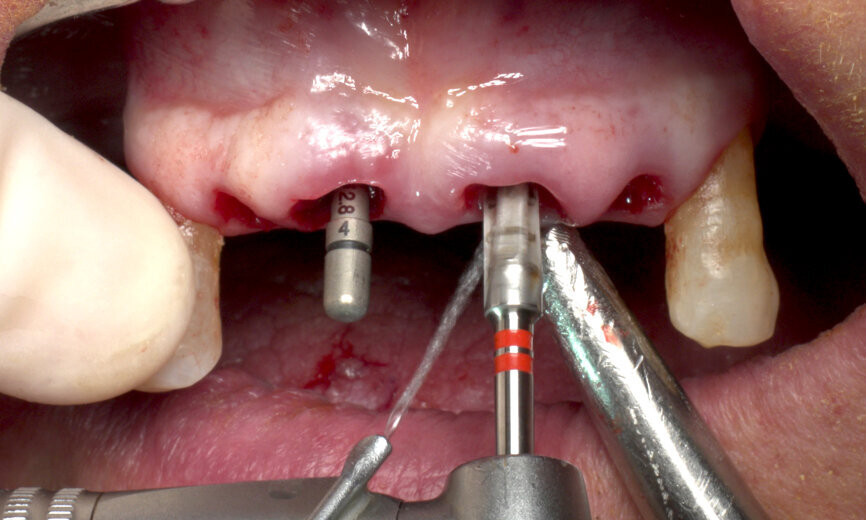

Furthermore, undersized drilling with continuous bone density assessment according to the operator’s own experience is mandatory to achieve the highest insertion torque, taking account of the biological bone situation and the mechanical properties of Roxolid. In this case, six implants (Straumann BLT, Regular Neck, Roxolid, SLActive, four of ⌀ 4.1 mm and two of ⌀ 4.8 mm) were placed with the handpiece at 45 N cm, with a final manual setting and monitoring of the insertion torque (Figs. 5 & 6). Careful orientation of the Loxim orientation marks is mandatory to maintain the desired parallelism of the SRA prosthetic screws.

After final implant seating, BLT Type 54 SmartPegs from Osstell were placed on each implant, and the ISQ level was measured and recorded at implant connection level. Values between 75 and 85 out of 100 were obtained, confirming the immediate loading possibility on all the implants (Figs. 7 & 8).